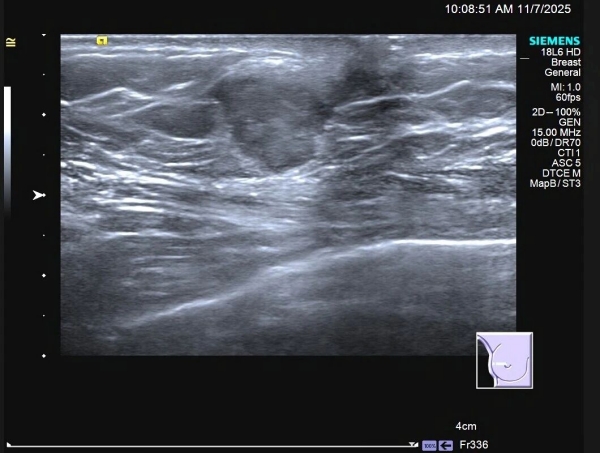

患者 C 先生,59 岁,因触及右乳肿物来到门诊部就诊,专科 B 超显示:右乳外侧近乳头处可见一低回声肿物,形态不规则,边缘模糊、成角,提示乳腺癌可能性大(BI-RADS:4C)。

在医生建议下,C 先生行 B 超引导下粗针穿刺活检术,病理显示:「浸润性癌」!

影像学检查

✦乳腺 B 超(首选,对乳腺肿物和腋窝淋巴结评价具有优势);